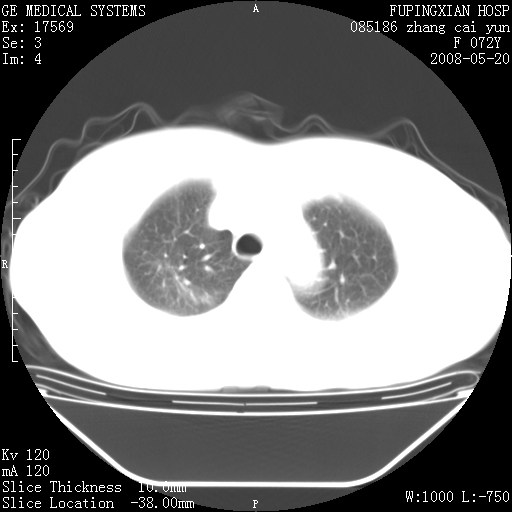

标题: CT13542:发热,咳嗽数日,经抗菌素治疗好转,请大家看排除 [打印本页]

标题: CT13542:发热,咳嗽数日,经抗菌素治疗好转,请大家看排除

上叶支气管略变窄并通畅,内壁光滑。考虑:单纯阻塞性肺炎!

右上叶支气管走行自然,未见明显管壁增厚等征像,另左主支气管起始部可见异常腔道向左侧延展左肺动脉干后方,与左下叶支气管相通,为左下叶支气管变异?

右肺上叶实变影,内见支气管充气征,右上叶支气管通畅,肺门区未见软组织密度影,抗炎治疗有效,考虑炎症,建议继续抗炎治疗复查。

考虑为:右肺上叶感染性病变。建议:1)继续抗炎治疗后复查。2)必要时行纤支镜检查。

右上肺实变,间内有支气管充气征,考虑炎症,建议抗炎后复查